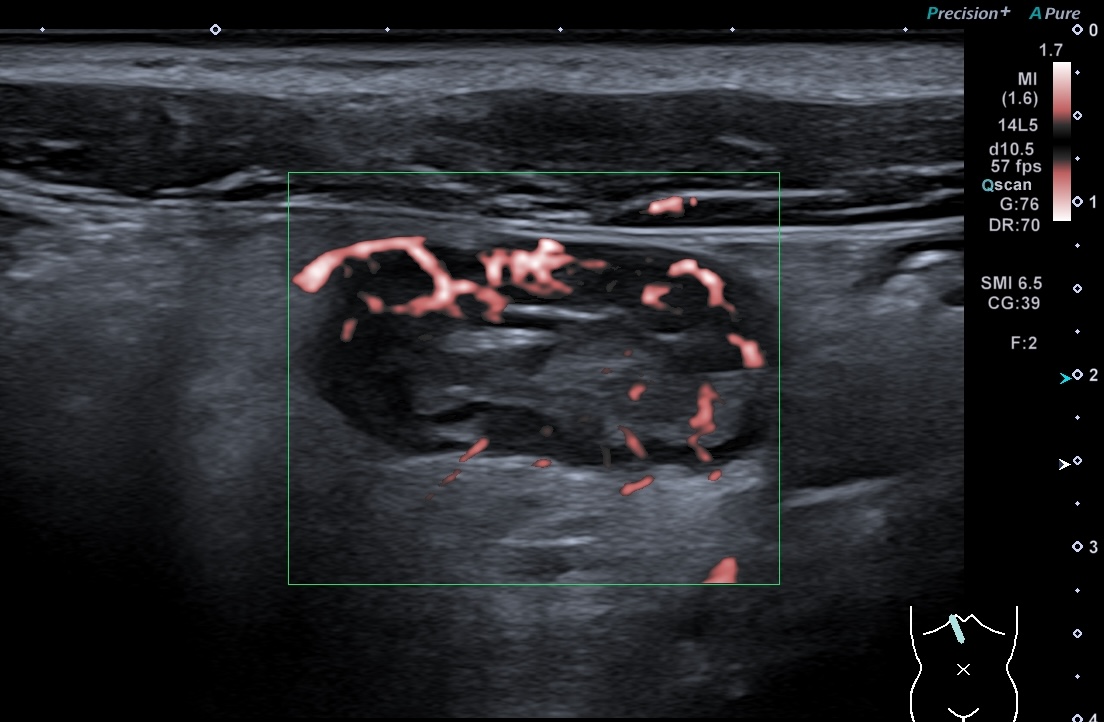

Doppler microcirculation LImberg 3 (activité intense de la paroi+ graisse)

même patient, pas d'indication de sens du flux